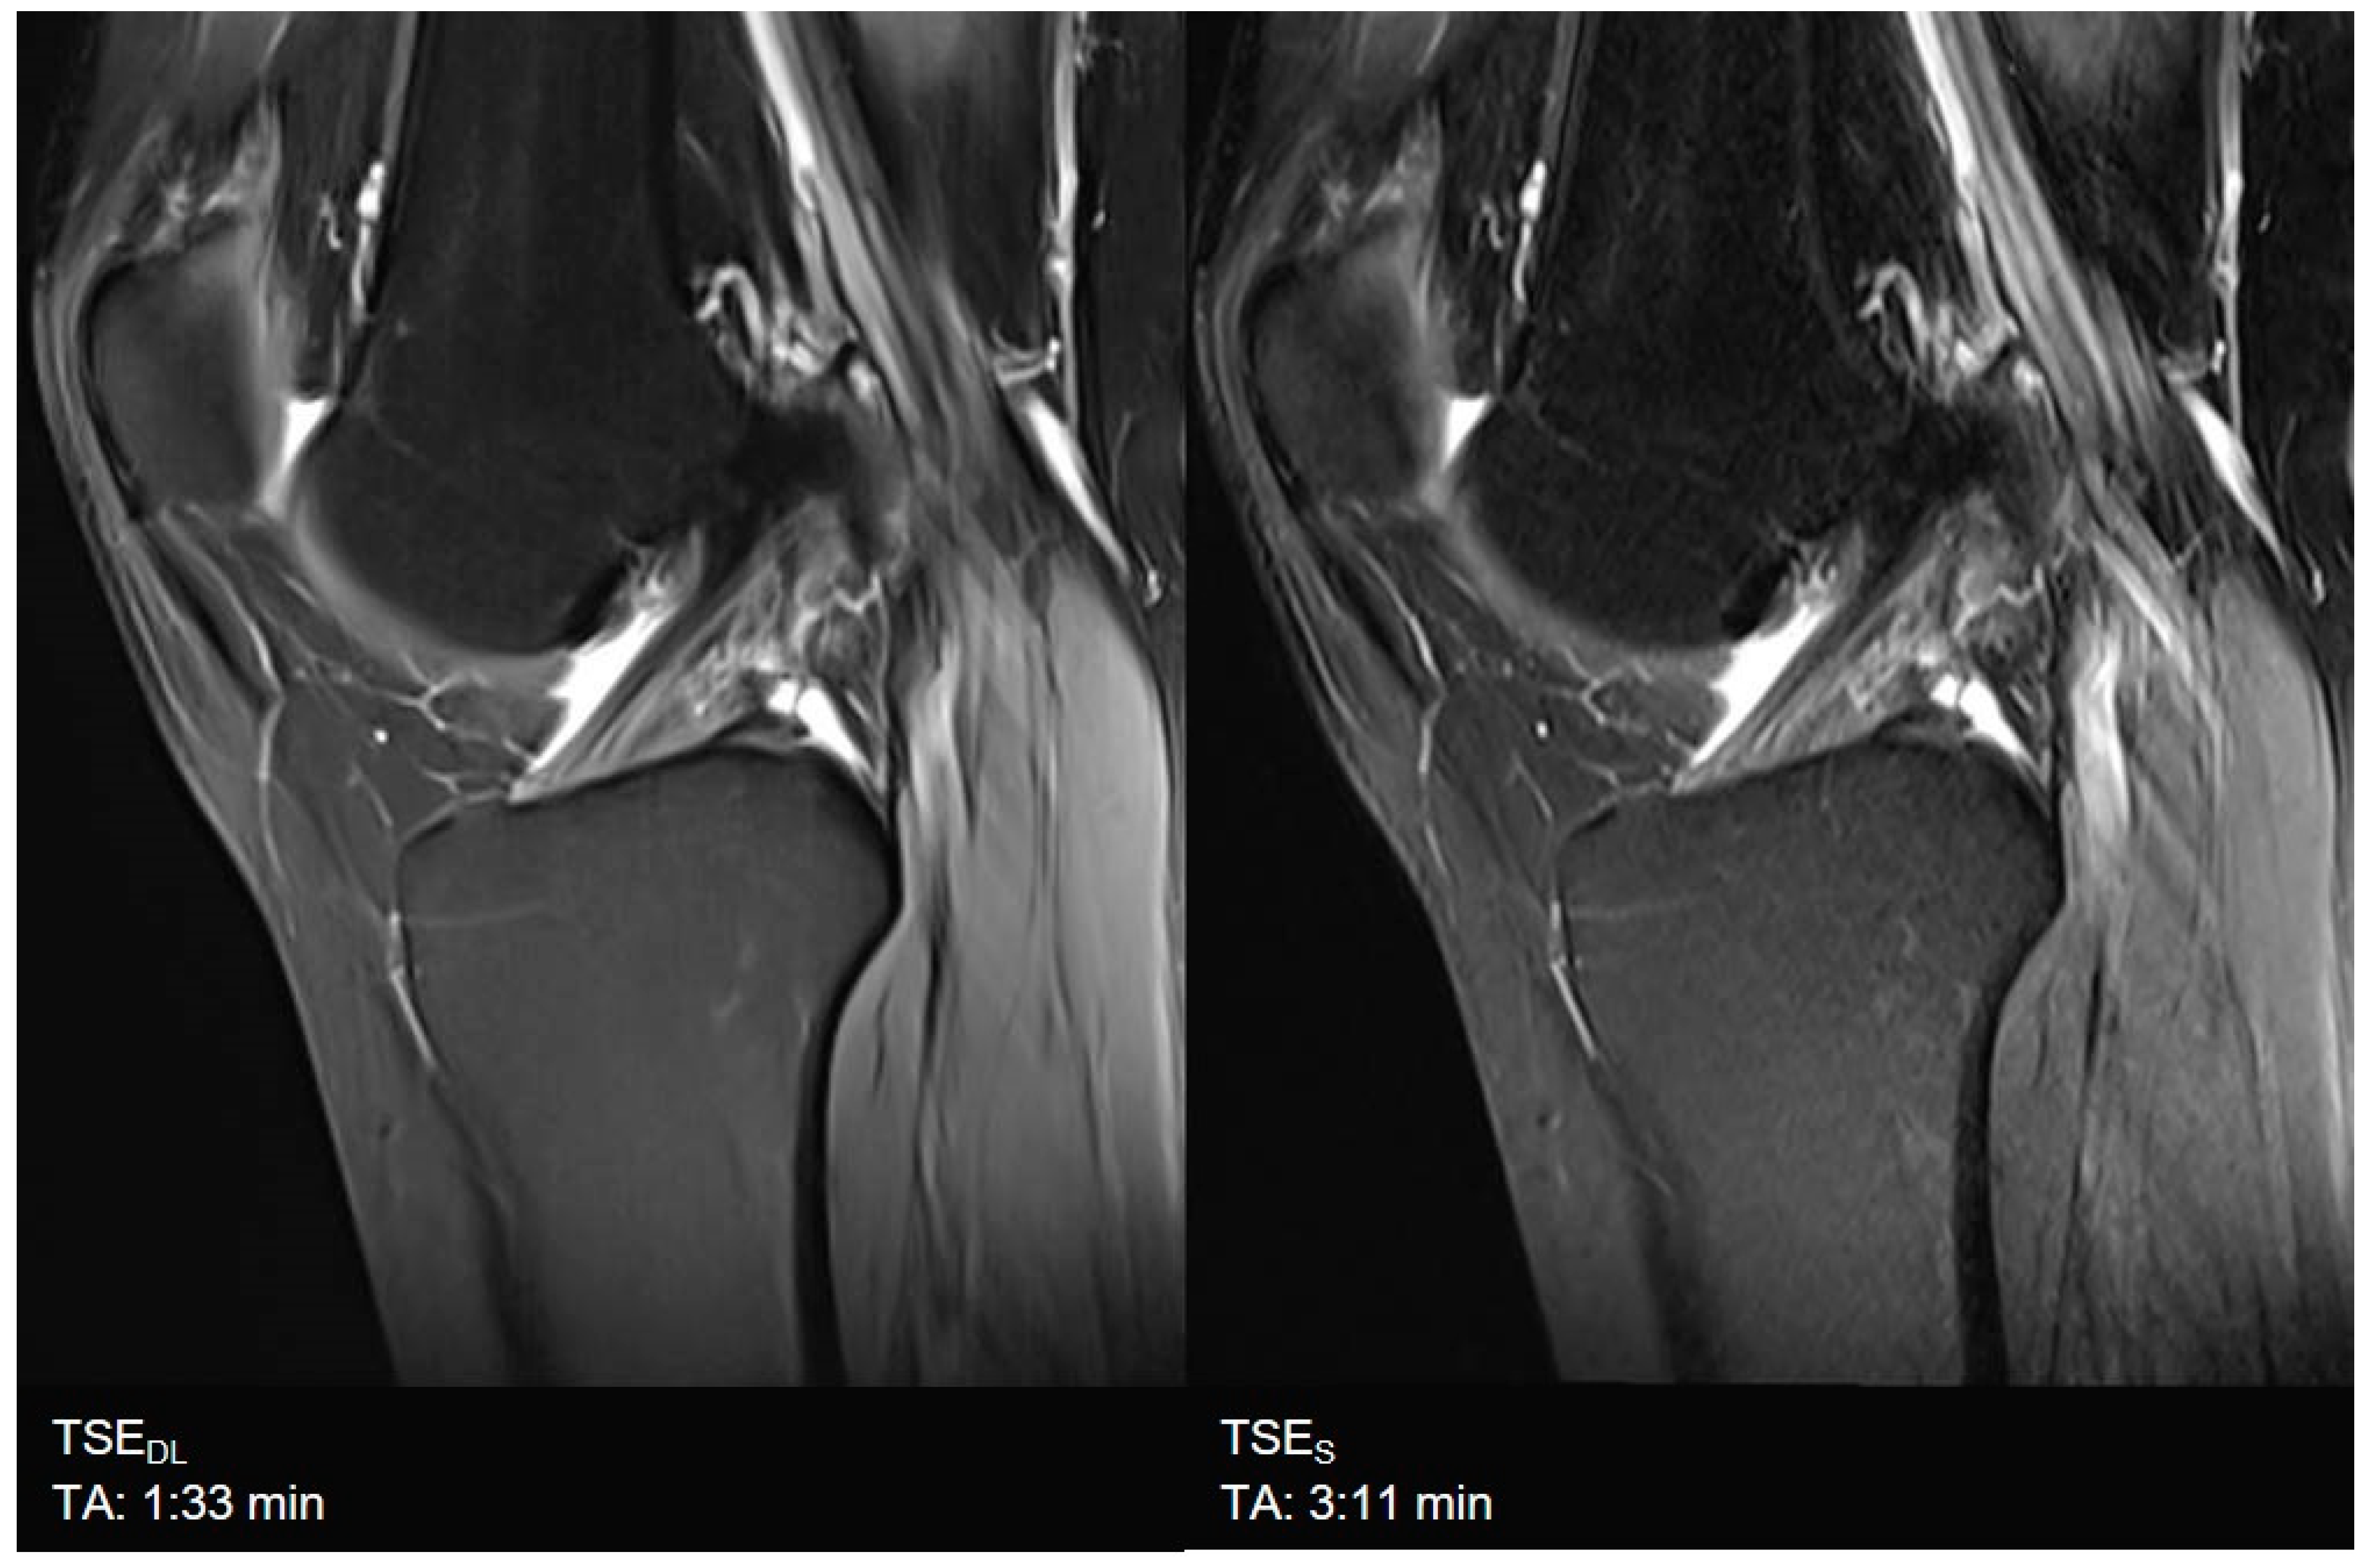

| Knee | TSES | TSE PD FS | coronal | 3:11 | 150 | 0.2 × 0.2 × 3.0 | 2 | 1 | 3 | 3790 | 44 | 150 | 100 | 14.6 |

| sagittal | 3:11 | 150 | 0.2 × 0.2 × 3.0 | 2 | 1 | 3 | 3790 | 44 | 150 | 100 | 14.6 | |||

| TSEDL | TSE PD FS | coronal | 1:33 | 150 | 0.5 × 0.5 × 3.0 | 1 | 1 | 3 | 3580 | 41 | 150 | 120 | 13.7 | |

| sagittal | 1:33 | 150 | 0.5 × 0.5 × 3.0 | 1 | 1 | 3 | 3580 | 41 | 150 | 120 | 13.7 | |||